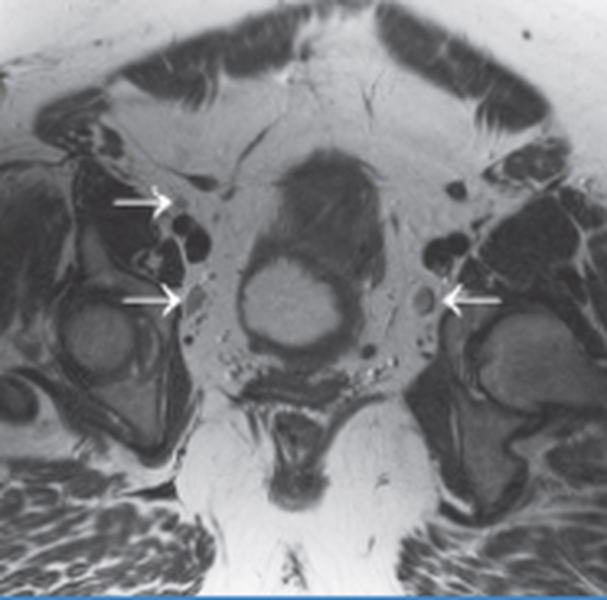

МРТ мужских половых органов, как правило, проводится по назначению врача-уролога, когда на приеме в ходе визуального осмотра и ручной пальпации возникли подозрения на патологию или травму. Являясь апробированным и высокоинформативным методом обследования, МР-скрининг помогает провести точную диагностику половых органов даже в тех случаях, когда стандартные методы диагностики (врачебный осмотр, УЗИ) не дают достаточных данных для установки правильного диагноза. Как правило, стандартное томографическое исследование половых органов мужчины в медицинских центрах СПб включает в себя детальное МРТ яичек, придатков мошонки и МРТ самого пениса. Сделать МРТ органов мошонки и члена рекомендуется при следующих симптомах и заболеваниях:

• Крипторхизм;